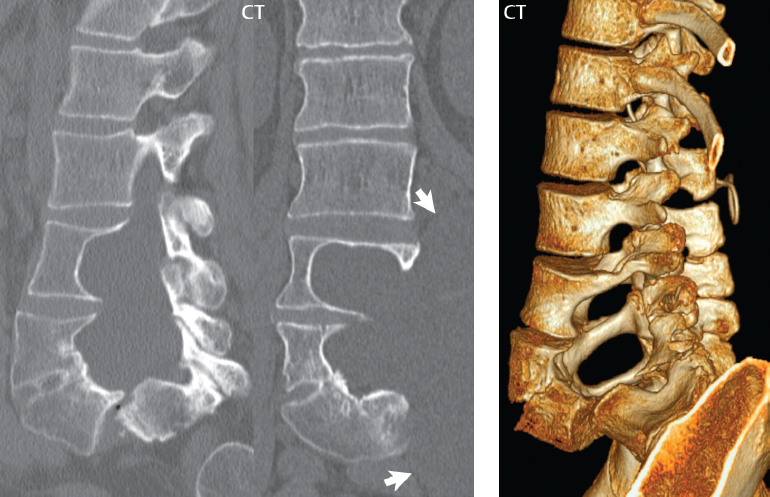

Spine(II) | Radiology Key

Spine(I) | Radiology Key